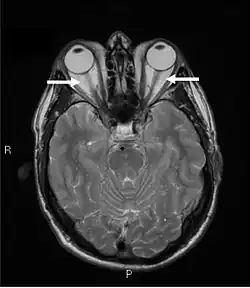

Orbital imaging is an integral tool for the diagnosis of Graves' ophthalmopathy and is useful in monitoring patients for progression of the disease. It is, however, not warranted when the diagnosis can be established clinically. Ultrasonography may detect early Graves' orbitopathy in patients without clinical orbital findings. It is less reliable than the CT scan and magnetic resonance imaging (MRI), however, to assess the extraocular muscle involvement at the orbital apex, which may lead to blindness. Thus, CT scan or MRI is necessary when optic nerve involvement is suspected. On neuroimaging, the most characteristic findings are thick extraocular muscles with tendon sparing, usually bilateral, and proptosis.